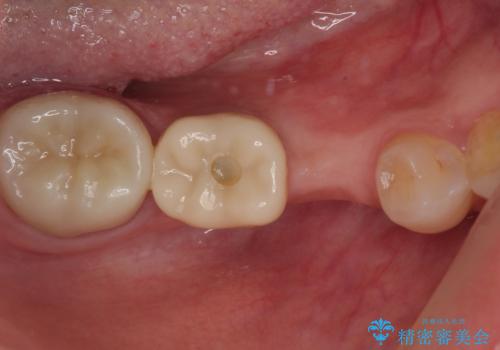

割れてしまった奥歯 インプラント治療

- 近医にて抜歯が必要と診断されたとのことで来院された患者様です。

術前の診査では、歯が破折している可能性が高いものの、確実に抜歯が必要と診断ができない状態でした。

状況次第では抜歯が必要となり、その際にはインプラント治療を行うことを了承いただいた上で、破折していない場合には根管治療を行うこととしました。

土台の材料を外して顕微鏡下で確認したところ、歯根にまで及ぶ破折が認められたため、インプラント治療を行うこととしました。